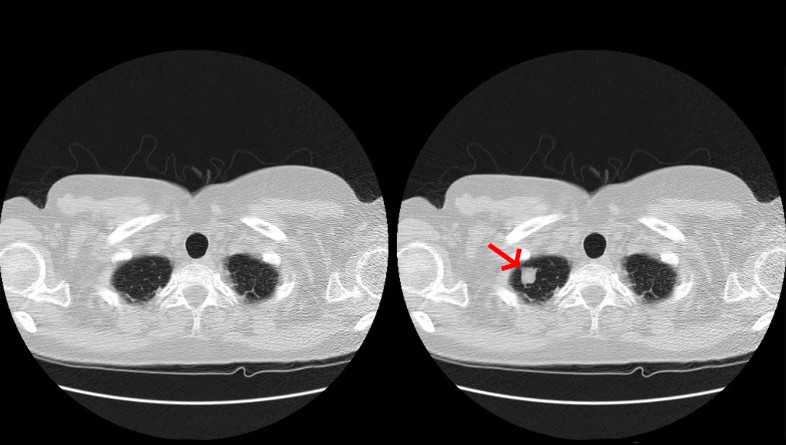

El malware que han desarrollado, según recoge The Washington Post, permite el alarmante hecho de alterar los resultados que las máquinas obtienen de las pruebas de las unidades de radiología. En otras palabras, y lo que es aún peor, permite que en los resultados de pacientes sanos aparezcan síntomas de cáncer, y que en los resultados de pacientes con cáncer puedan eliminarse los rastros de tumores que hagan saltar las alarmas.

La investigación ha arrojado resultados sorprendentes. Alterando hasta 70 tomografías, el equipo ha logrado engañar a tres radiólogos expertos en tests ciegos mediante modificaciones que el sistema realiza con aprendizaje automático. En el caso de tumores fabricados, los radiólogos identificaron cáncer el 99 por cientos de las ocasiones, y en el caso de que los signos de cáncer fueron eliminados de pacientes que sí lo padecían, los radiólogos fueron engañados en el 94% de las veces.

Lo peor es que incluso siendo avisados de que los escaneos habían sido modificados en una nueva tanda de 20 pruebas, con 10 de ellos modificados y 10 estando intactos, también erraron, pues pensaron que los tumores falsos eran reales el 60% de las veces. Cuando los resultados fueron al contrario, tras haber eliminado tumores cancerígenos, los radiólogos fueron engañados el 87% de las veces, pues concluyeron que los pacientes estaban sanos.